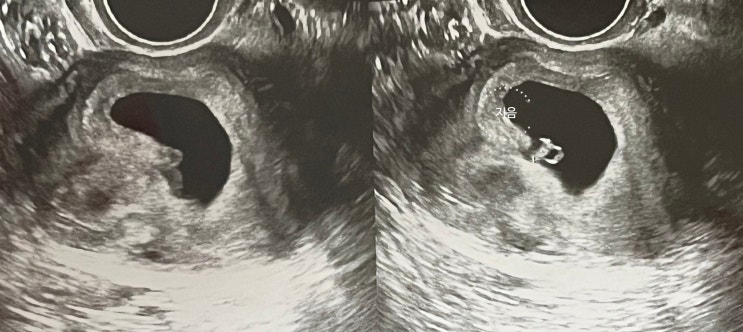

[임신일기] 6~7주 차 난황에 아기발견, 심장소리, 임신초기 출혈

[임신일기] 동결이식 4~5주 차 아기집, 난황 확인, 임신초기 출혈